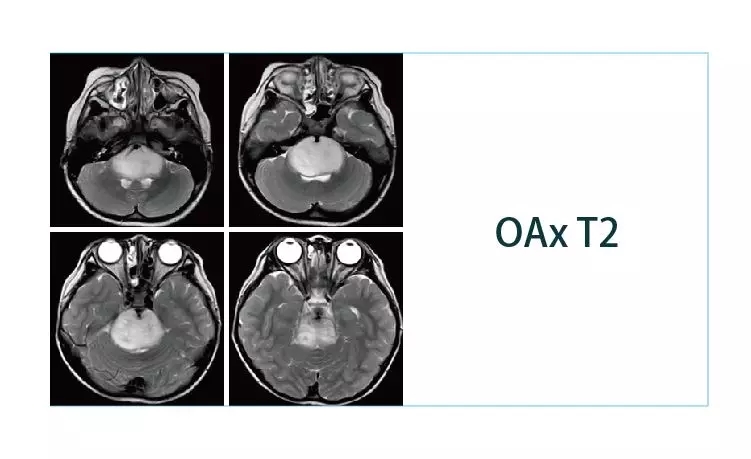

【朗润影像档案】磁共振影像病例分享(编号20190329)